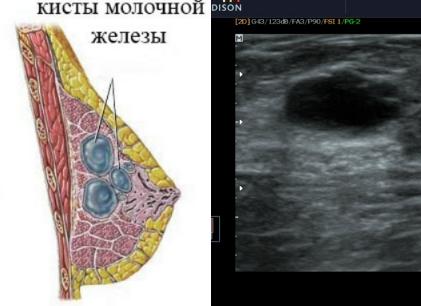

Что такое киста молочной железы и как ее лечить? Это распространенная патология с жидкообразным содержимым, которая образуется в протоках молочной железы.

Киста — полость, которая ограничивается соединительной капсулой и заполняется жидкостью. Новообразование бывает круглым, овальным или неправильной формы. Может колебаться в размерах от нескольких миллиметров до нескольких сантиметров.

Обычная киста имеет гладкие и ровные внутренние стенки. У атипичной имеются разрастания внутрь полости. Избавляет ли лечение народными средствами от кисты молочной железы?